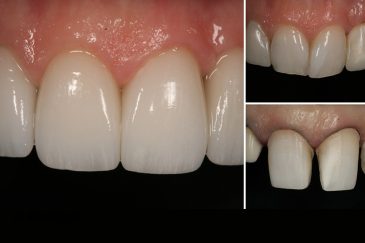

دندانپزشکی زیبایی

طراحی لبخند هالیوودی با متدهای لمینت سرامیکی دندان و کامپوزیت ونیر در کنار اصلاح فرم، خدمات بلیچینگ و روکش دندان، زیبایی چهره شما را تکمیل میکند.ترمیم دندان